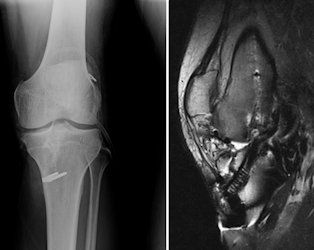

Bağ cerrahisi sırasında kullanılan metal ve biyobozunur (vücut içinde eriyerek kaybolan) implantlar vücutla büyük uyum gösterirler ve çoğu zaman çıkartılmaları gerekmez. Nadir de olsa, zayıf yapılı kişilerde cilt altında rahatsızlık veren veya eklem içi uygun olmayan şekilde yerleştirilen implantların çıkartılması gerekli olabilir (Resim 2). Hastaların %2-3’ünde, biyobozunur implantların erimesi sırasında yol açtığı reaksiyonlar için çıkartılmaları gerekir. Bu durum genellikle ilk cerrahiden 1 yıldan fazla geçen hastalarda ortaya çıkar ve bağ sağlamdır.

Eğer doktorunuz revizyon cerrahisine karar verdi ise ciddi bir ameliyat öncesi planlama gereklidir. Dikkatli bir muayene ile eşlik edebilecek yan bağ yaralanmaları, menisküs hasarları, kas gücü, önceki yara izleri ve ilk cerrahide kullanılmış olan dokular değerlendirilir. Ardından röntgen grafileri ile eklemin genel durumu, tünel yerleşimleri, kullanılan implantlar ve dizinizdeki kıkırdak aşınmasının miktarı değerlendirilir. Bacaklarınızda bir kemik eğriliği varsa bunun için aks grafisi adı verilen kalça, diz ve ayak bileği eklemini içine alan boy grafileri çekilebilir. İlk cerrahide açılan tünellerde genişleme varsa, bu revizyon sırasında kullanılan dokuların kemiğe tespitini olumsuz etkileyecektir, şüpheli bir durumda tünel genişlemesi bilgisayarlı tomografi ile değerlendirilebilir. Son olarak manyetik rezonans görüntüleme ile dizinizdeki bütün yumuşak doku ve kemik yapılar ayrıntılı olarak incelenir.Bütün bu incelemeler sonrasında doktorunuz revizyon cerrahisinin şeklini, kullanılacak olan doku kaynaklarını, tek veya iki aşamada mı cerrahi yapılacağını, menisküs, kıkırdak ve diğer bağlarınıza bir işlem gerekip gerekmediğini ve kemik dizilimini düzeltecek ameliyatlara ihtiyacınızı belirler. Son olarak yapılan artroskopik inceleme ile eklem içi yapılar değerlendirilir ve yapılacak işlemin devamının nasıl olacağına karar verilir (Resim 3)